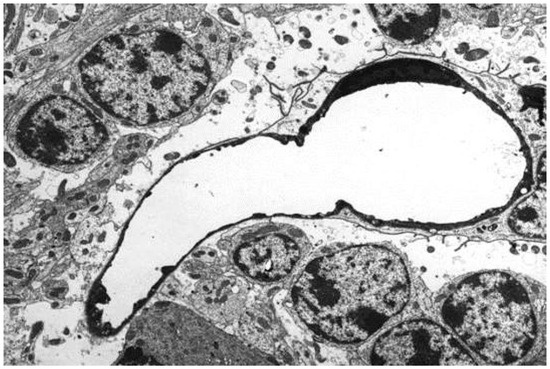

In the first study of ETX-induced retinal injury in rats [23], six-week-old, Sprague Dawley animals were given an intraperitoneal injection of a 1:300 dilution of a batch of ETX, which was equivalent to 69,000 mouse minimum lethal doses of this toxin. At 3 h post-injection of toxin, rats were killed by perfusion fixation with 4% paraformaldehyde, with one eye then fixed in Davidson’s fixative for light microscopy and the other with 2.5% glutaraldehyde for electron microscopy. For the immunohistochemical detection of plasma albumin extravasation, a goat anti-rat albumin antibody was used. Control rats were given a similar volume of physiological saline and their eyes were similarly processed. When rats were given this acute dose of ETX [23], severe ultrastructural retinal microvascular injury was found. The most severe endothelial damage was characterized by marked attenuation and increased electron density (Figure 1). Prior to the development of endothelial coagulation necrosis, there was frequent blebbing of the luminal surface and occasional platelet adhesion (Figure 1), but not thrombosis. These retinal microvascular lesions resembled those found in the brain microvasculature of sheep [2,3] and mice [24] exposed to ETX (Figure 2). To further examine this BRB breakdown, immunohistochemical studies used endogenous albumin extravasation as a surrogate marker of increased vascular permeability [23]. In ETX-treated rats, there was diffuse albumin extravasation in all retinal layers, which was particularly prominent around small blood vessels, and albumin also flooded the cytoplasm of damaged endothelial cells (Figure 3). This widespread retinal albumin leakage confirmed the presence of generalized vasogenic oedema and resembled the albumin extravasation found in ETX-exposed sheep (Figure 4) [2,3] and rat brains [23]. Microvascular albumin leakage is particularly deleterious to the retina as regulation of albumin transport is critical for maintaining appropriate protein gradients in the retina and subsequent fluid movement [12,13].

Figure 2.

Electron micrograph of similar capillary damage to Figure 1 produced by ETX in the cerebellar granular layer of a sheep. As in rats, the endothelium is markedly attenuated and electron-dense, with nuclear pyknosis. Perivascular astrocytic end-foot processes are severely swollen as a result of increased vascular permeability. Uranyl acetate and lead citrate. ×3750.